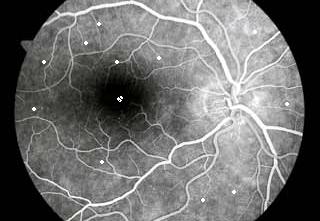

Μια αποκαλυπτική εξέταση για διάγνωση αλλοιώσεων απο σακχαρώδη διαβήτη, παθήσεων της ωχράς και άλλων παθήσεων του οφθαλμού. Γίνεται με την ενδοφλέβια χορήγηση μιας φθορίζουσας ουσίας που μας επιτρέπει , με μιά ειδική κάμερα να φωτογραφίσουμε τον βυθό του ματιού και την κυκλοφορια μεσα στα αγγεία του ματιού. Κατόπιν εαν χρειαστεί παρεμβαίνουμε με laser.